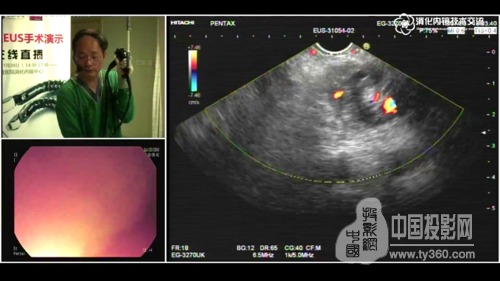

圖3:手術畫面實時傳送到技術研討會現場

數字化手術室,通過在手術室這一特殊環境中實現各種設備和信息的高度集成、互聯互通,為醫生提供及時、豐富、準確的患者信息,并實現多方人員的最優化協作和信息共享。手術室不再是信息孤島,它不僅與外部觀摩室、示教室、培訓室、會議室等互聯互通,還可以隨時面向全球直播。而且我們的醫生在手術前還可以輕松調閱HIS、PACS、LIS等各個業務系統的病患信息,術中所有醫護人員也可輕松同步獲取手術視頻及監護信息。

華平股份智慧醫療產品總監,長海醫院數字化手術室項目負責人易曉表示:“在語音和圖像輸出方面,我們采用了華平獨有的光纖影像傳輸技術,實現廣播級影像傳送,1080P的圖像質量,可達到會診級別,完全滿足醫學專家學術研討對圖像質量的要求。”